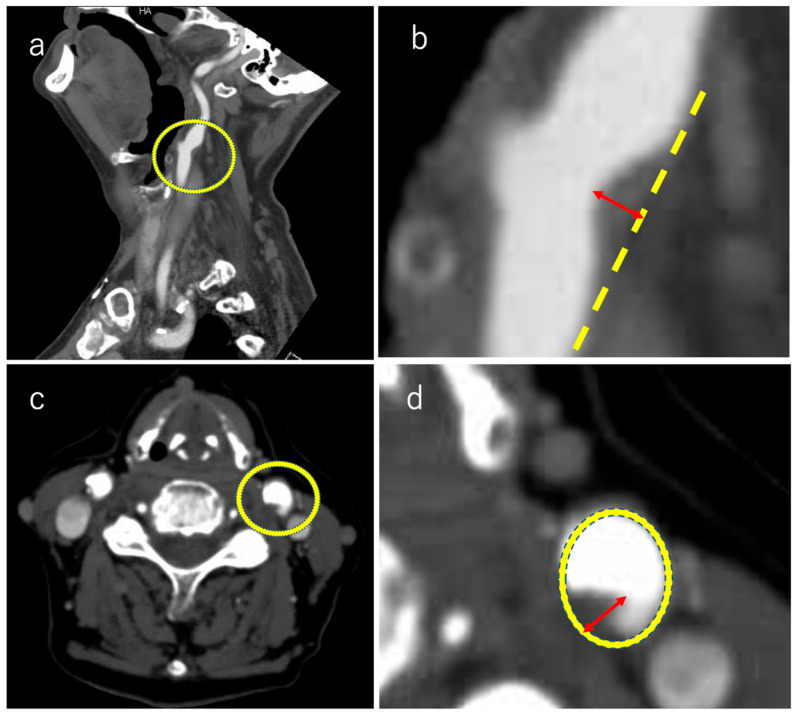

Objectives: While traditionally, carotid plaques with significant stenosis have been considered major embolic sources, recent evidence suggests that even non-stenotic small plaques with a <50% stenosis rate may contribute to cerebral infarction. Herein, we evaluated the relationship between non-stenotic small plaques and embolic stroke of undetermined source (ESUS) using computed tomography angiography (CTA). Materials and Methods: We retrospectively reviewed our single-institutional database of hospitalized patients with stroke between April 2017 and December 2022 and enrolled them with ESUS. We evaluated the presence or absence of non-stenotic carotid artery plaque lesions ipsilateral and contralateral to the cerebral infarction lesion using CTA. A neurologist, blinded to the stroke side and all other clinical information, reviewed each CTA and viewed the axial and sagittal CTA source images. In each image, a line perpendicular to the vessel wall was drawn and the plaque diameter was measured. The largest part was considered as the maximum plaque diameter. Results: A total of 951 patients with stroke were hospitalized during the study period. Among these, 35 patients with unilateral anterior circulation ESUS were enrolled. Plaque prevalence > 3 mm was compared between the carotid artery on the ESUS side and contralateral carotid artery. The prevalences were 31% and 8% on the ESUS and contralateral sides, respectively. Plaques > 3 mm were often found on the ESUS side. Conclusions: Patients with ESUS were more likely to exhibit non-stenotic plaques of ≥3 mm in the infarcted carotid artery than in the contralateral carotid artery. Thus, small non-stenotic plaques may be the embolization source in ESUS, and CT angiography is useful for these evaluations.